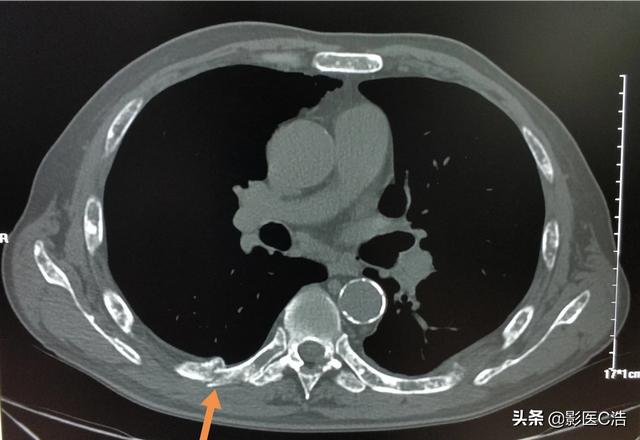

Il y a quelques jours, un patient atteint d'un cancer du poumon avec métastases osseuses a été diagnostiqué. Ses symptômes sont des douleurs lombaires de longue durée, ils ont toujours pensé qu'il s'agissait d'un claquage musculaire lombaire ou d'une hernie discale lombaire, mais ils ne se sont pas inquiétés, la douleur est vraiment sérieuse et les symptômes nerveux des membres inférieurs sont apparus. ...... recherche détaillée des antécédents médicaux, découverte que le patient présente depuis longtemps des symptômes de toux, ce qui permet de soupçonner un cancer du poumon avec métastases osseuses, l'examen tomodensitométrique du poumon a révélé que le foyer principal ...... est un énorme cancer du poumon.

Quel type de douleur doit alerter sur la présence de métastases osseuses ? Les métastases osseuses sont une manifestation fréquente des tumeurs malignes à un stade avancé. La tumeur primaire présente dans d'autres parties du corps se métastase dans les os par les voies sanguines et lymphatiques, formant ainsi des métastases osseuses. Les métastases osseuses signifient que le tissu osseux normal a été détruit et remplacé par du tissu tumoral. Les métastases osseuses peuvent être classées en trois types selon la spécificité de la lésion : le type ostéolytique, le type ostéogénique et le type mixte. Les sites courants de métastases osseuses sont l'os de la diaphyse moyenne (colonne vertébrale et bassin), les côtes et la métaphyse inférieure, l'os de la diaphyse moyenne étant le plus courant, ce qui est lié aux caractéristiques de l'apport sanguin dans cette zone. Comme le montre le cercle ci-dessous, les métastases osseuses sont multiples et la colonne vertébrale est en mauvais état.